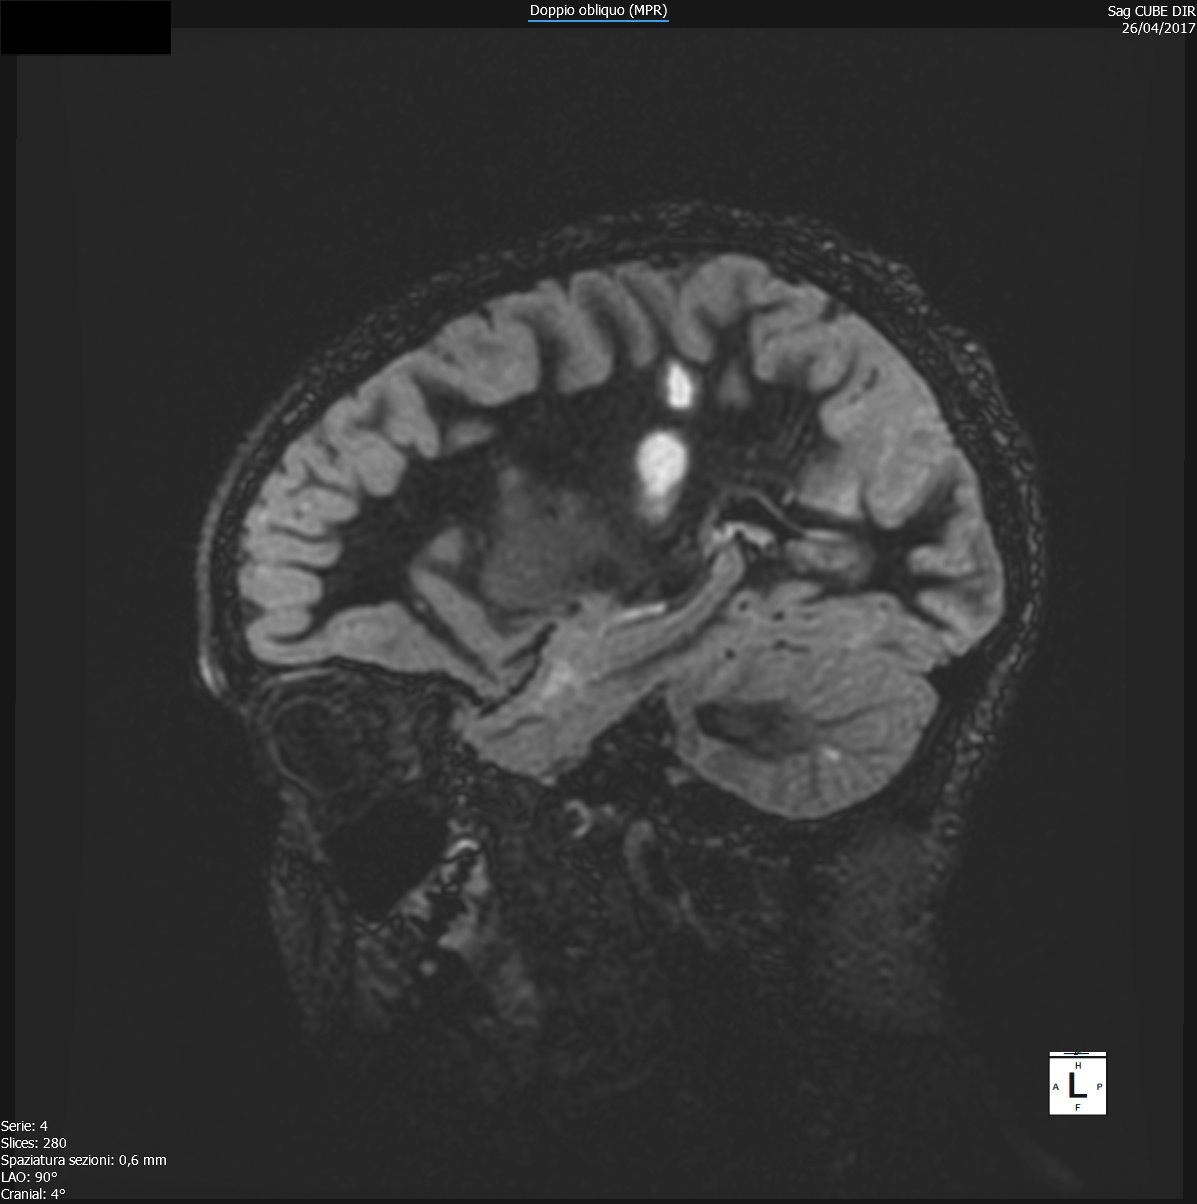

Durante il ricovero è stata eseguita RM di encefalo e midollo con mezzo di contrasto, che confermava la presenza di aree di alterato segnale già note a livello sovra- e sotto-tentoriale e il coinvolgimento midollare a livello di C1-C2, C4-C5, D10-D11 queste ultime con enhancement al contrasto, alterazioni compatibili con lesioni demielinizzanti ad andamento recidivante-remittente in fase attiva (Figure 1-3).